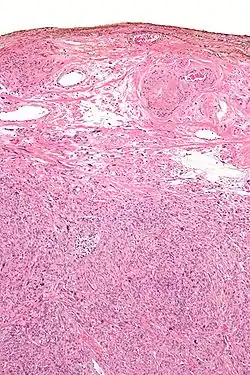

In histology, silver nitrate is used for silver staining, for demonstrating reticular fibers, proteins and nucleic acids. For this reason it is also used to demonstrate proteins in polyacrylamide gel electrophoresis (PAGE) gels. It can be used as a stain in scanning electron microscopy.[14]